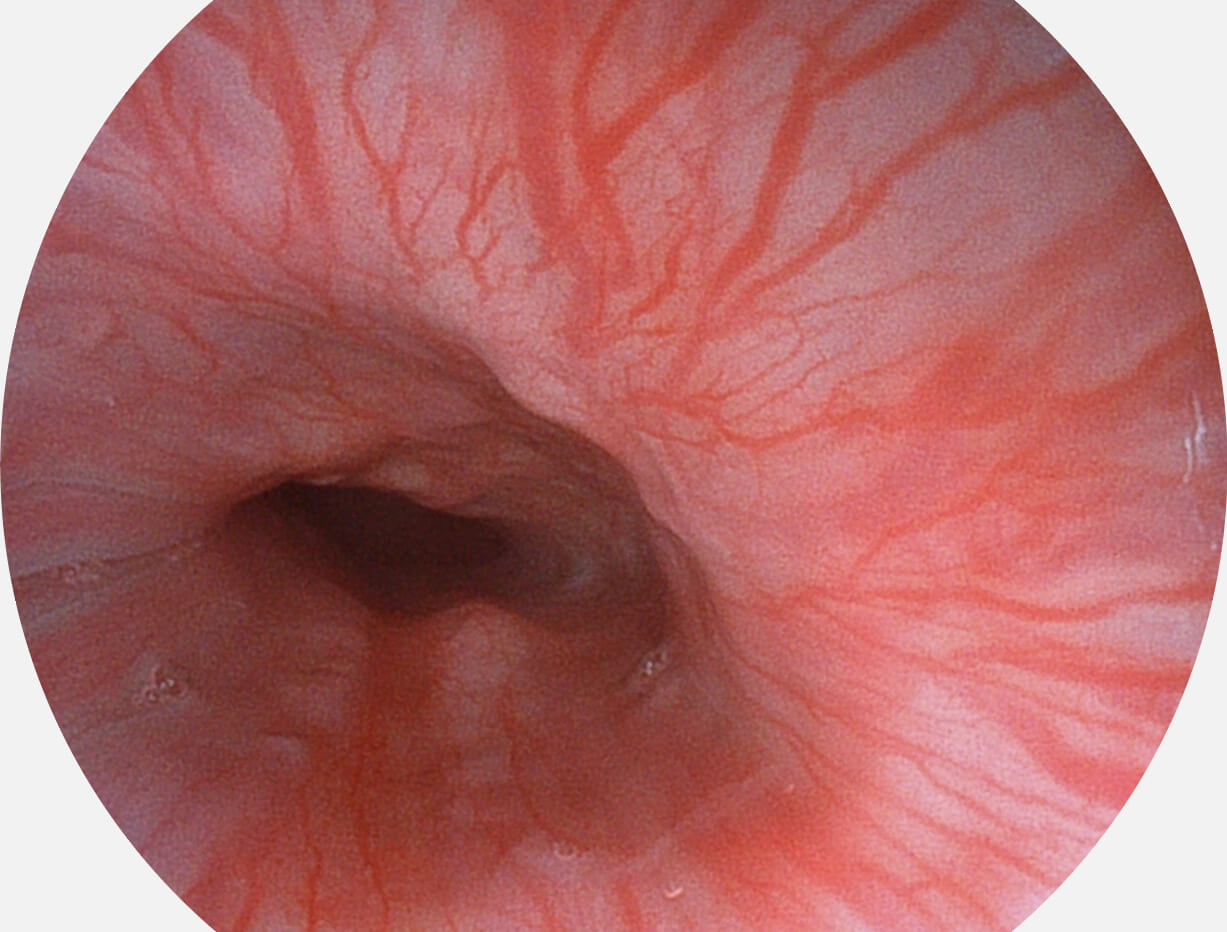

图像具有高亮度、高黏膜血管颜色对比度的特点,且不改变粘液、食物残渣、粪便的基本颜色,可在中远景下进行观察,助力消化道早期疾病的诊断。

SFI图像